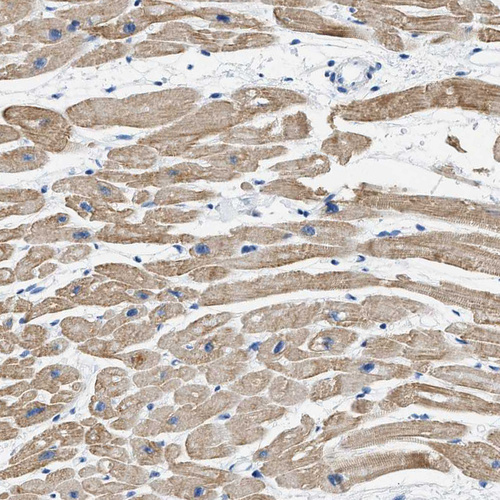

Immunohistochemistry analysis in human heart muscle and prostate tissues using HPA018174 antibody. Corresponding HHATL RNA-seq data are presented for the same tissues.